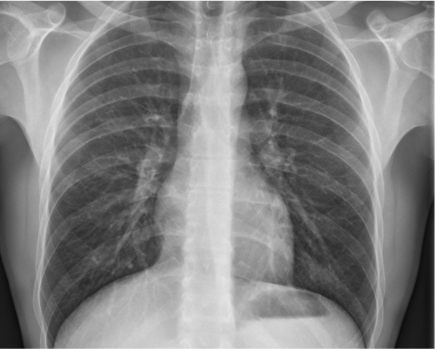

Quel avenir pour l’imagerie thoracique dans les 10 ans ?